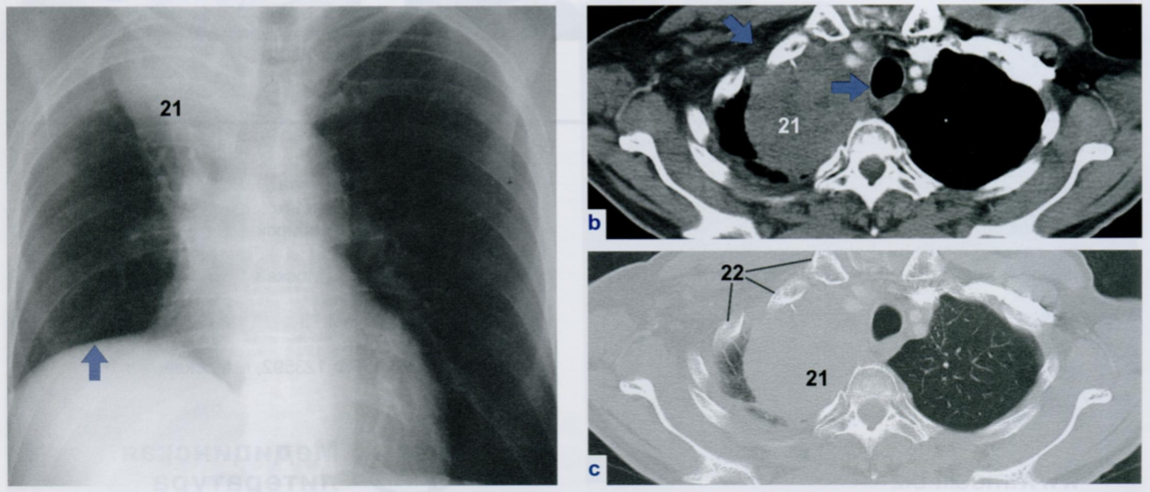

Оцените снимки.

Что отмечено стрелками? Мы можем это расценить как патологическое утолщение плевры?

Некоторые участки плевры могут выглядеть расширенными или неровными, и это не следует принимать за патологическое утолщение.

В частности, линия париетального листка плевры хорошо видна в ЗПП (первый снимок). Она имеет волнистый характер из-за того, что повторяет анатомические контуры межреберных промежутков (сравните со вторым снимком).

На втором снимке верхушечная плевра расположена по касательной к ходу рентгеновского излучения и поэтому выглядит, как сопровождающее затенение вдоль нижнего края второго ребра (22).